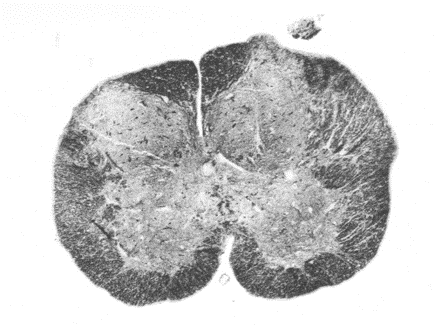

A

spinal cord. dorsal horn grey matter at the top half and ventral at the bottom